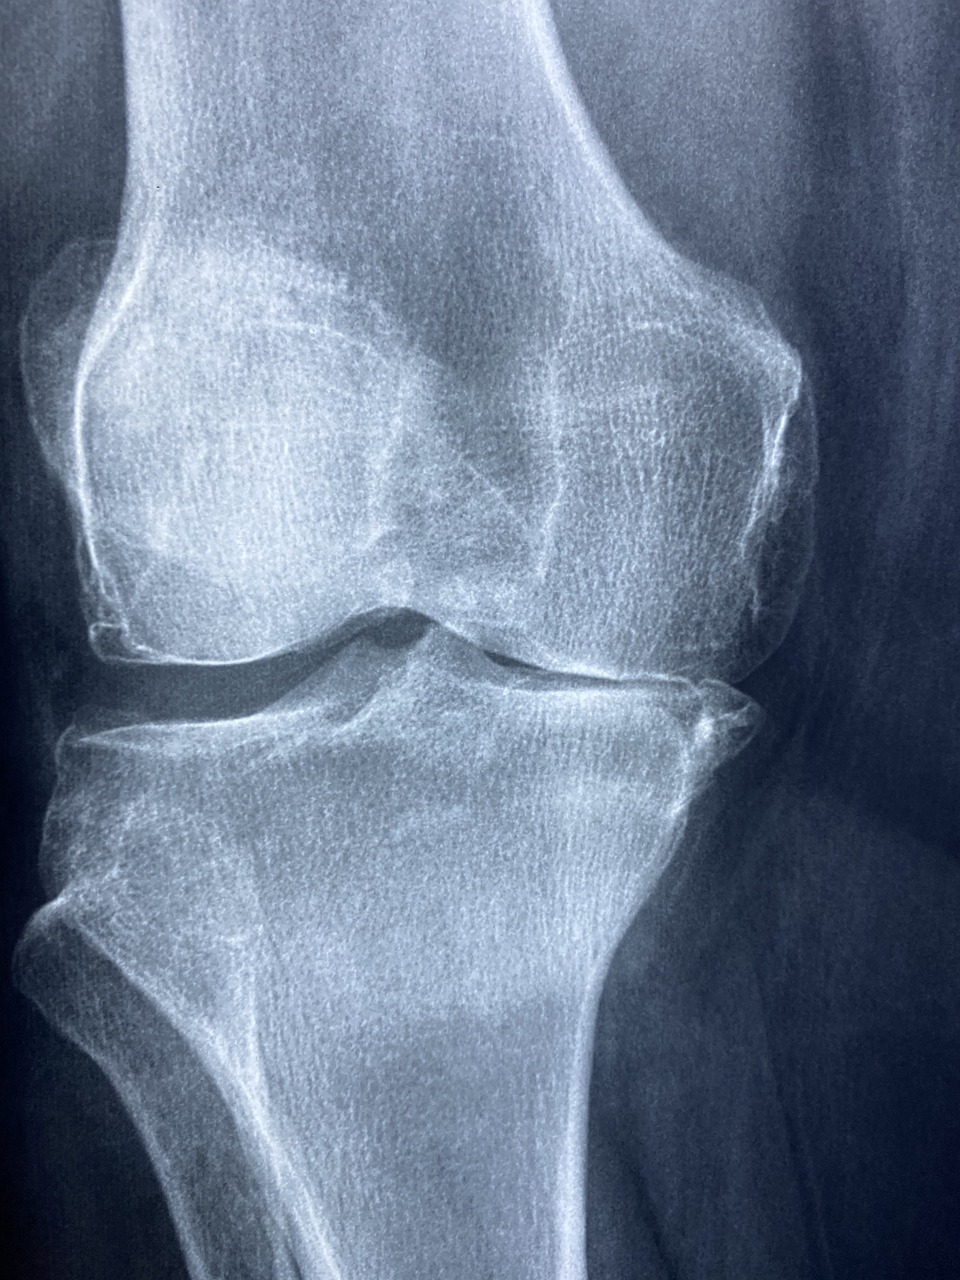

퇴행성 관절염의 진단방법

퇴행성 관절염의 진단은 환자의 증상과 신체검사, 그리고 영상 촬영 등을 통해 이루어집니다.

X선검사는 연골이 얇아진 정도와 관절의 변형 여부를 확인하는 데 유용하며, 경우에 따라 MRI를 통해 연골이나 주변 조직의 상태를 더욱 세밀하게 평가하기도 합니다. 또한, 의사는 관절에 염증이 있는지, 관절을 움직일 때 불편함이 있는지를 검사합니다,